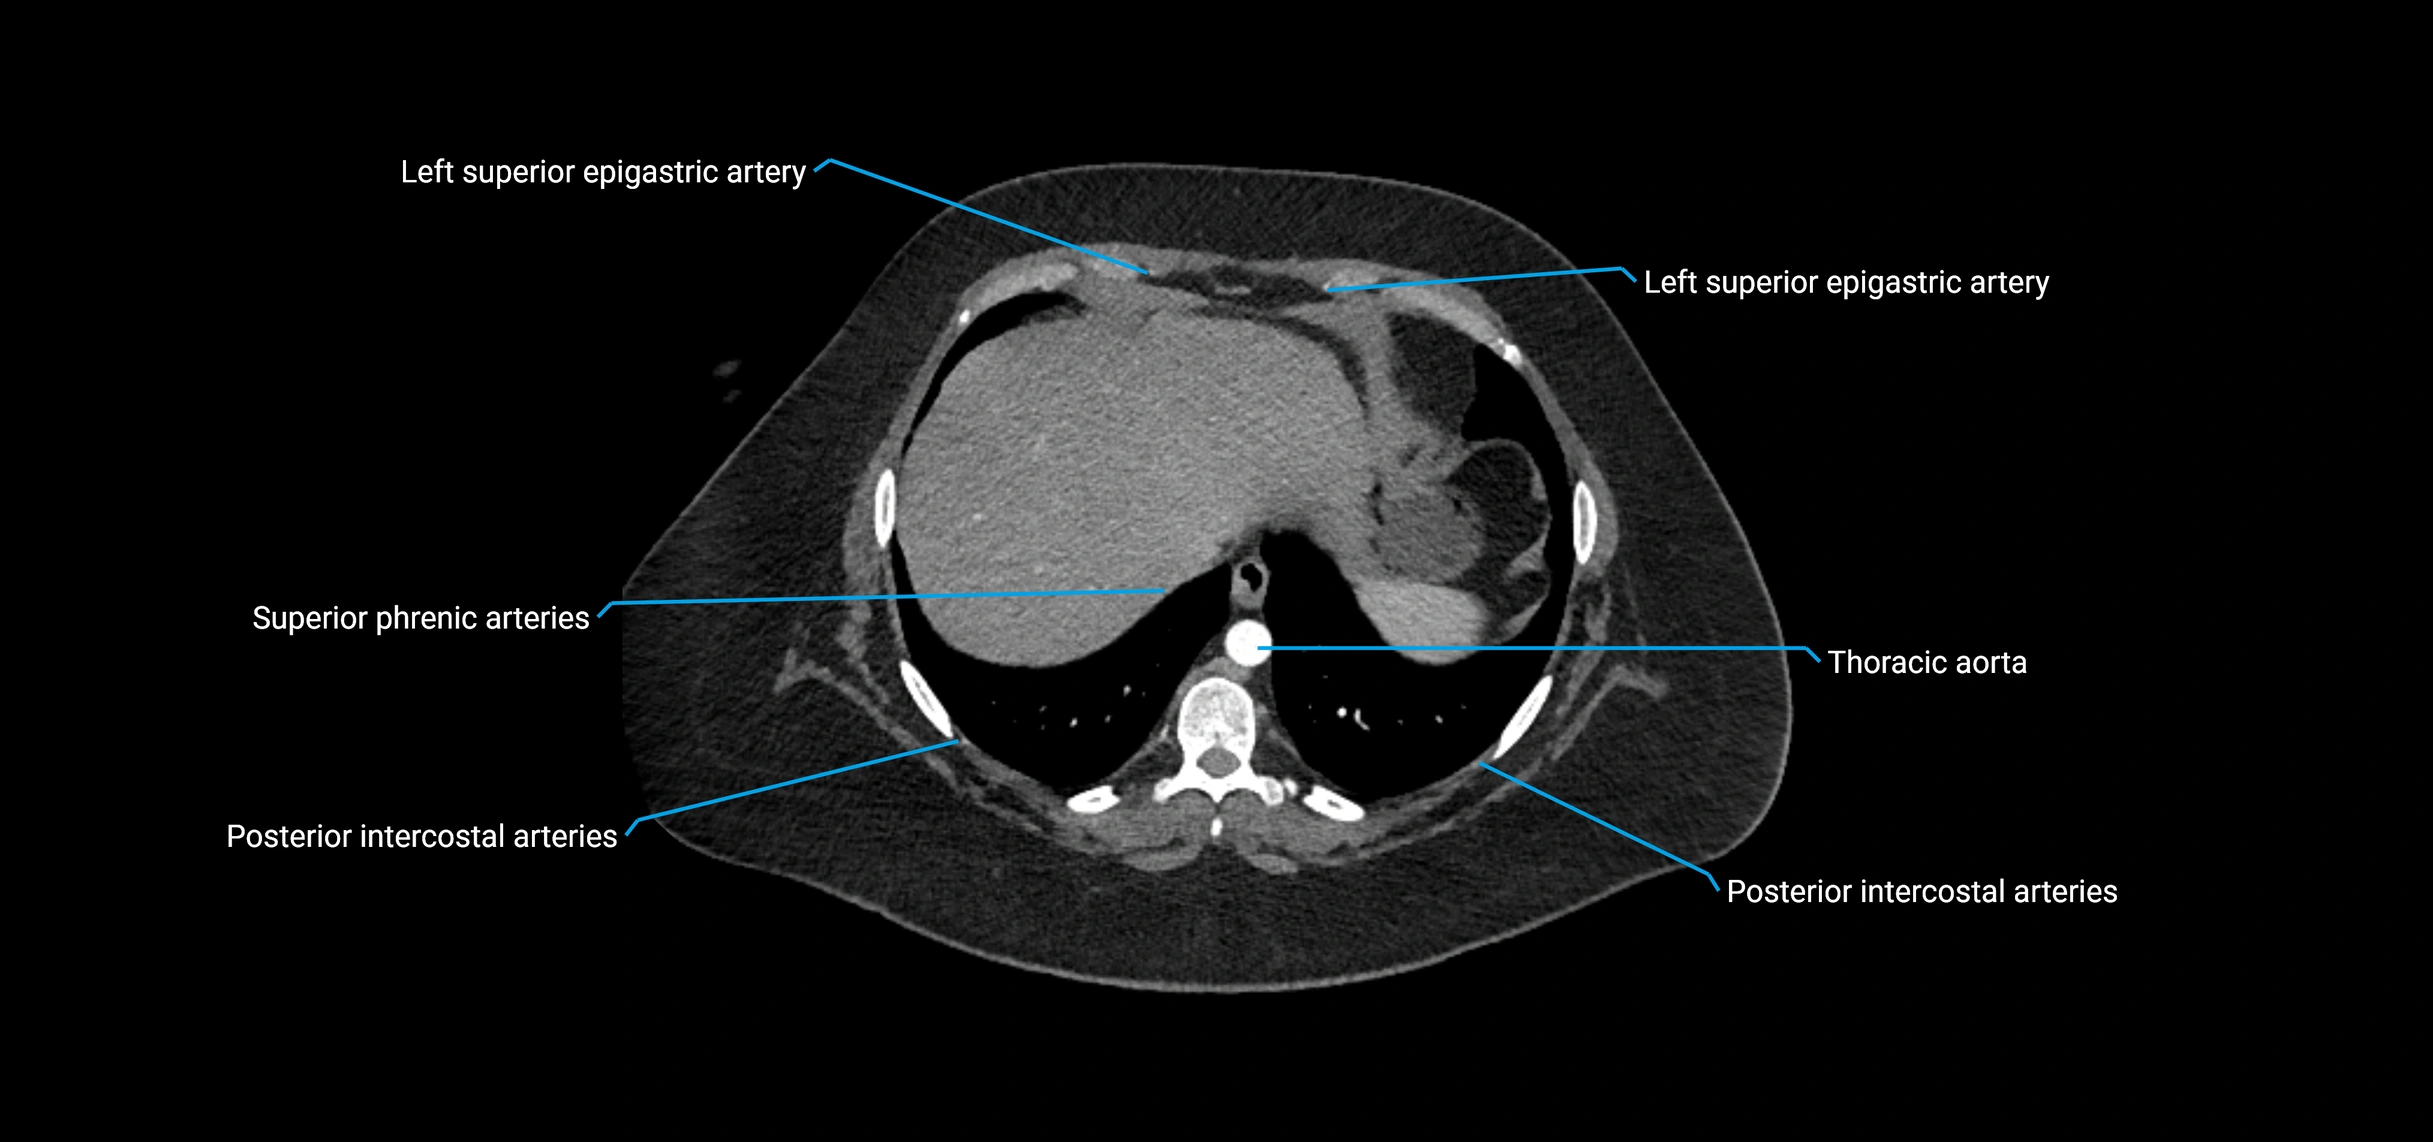

CT images

image

CT Appearance

Non-contrast CT:

• Appears as a tubular soft tissue structure anterior to vertebral bodies

• Calcified atherosclerotic plaques appear as hyperdense foci along the wall

• Useful for screening abdominal aortic aneurysm (AAA) size and mural calcification

Contrast-enhanced CT (CTA):

• Gold standard for abdominal aortic imaging

• Provides excellent detail of lumen, wall, aneurysm, thrombus, and branch vessels

• Multiplanar and 3D reconstructions help in aneurysm measurement, stent graft planning, and dissection evaluation

• Detects acute rupture, traumatic injury, or occlusion with high sensitivity